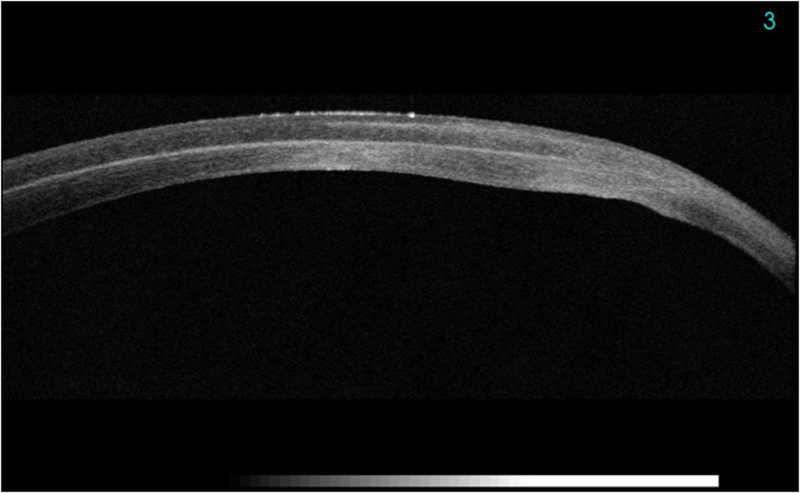

La córnea posee cinco capas histológicamente bien diferenciadas de superficie a profundidad: epitelio, membrana de Bowman, estroma, membrana de Descemet (MD) y endotelio. Las capas de mayor reflectividad en la OCT corresponden a la superficie anterior corneal y al límite posterior de la córnea con la cámara anterior

1. Se puedenobservar corneas sanas (distinguimos epitelio, estroma y endotelio) (

Figura 1). También se pueden estudiar adelgazamientos corneales como el queratocono (

Figura 1. OCT corneal normal.